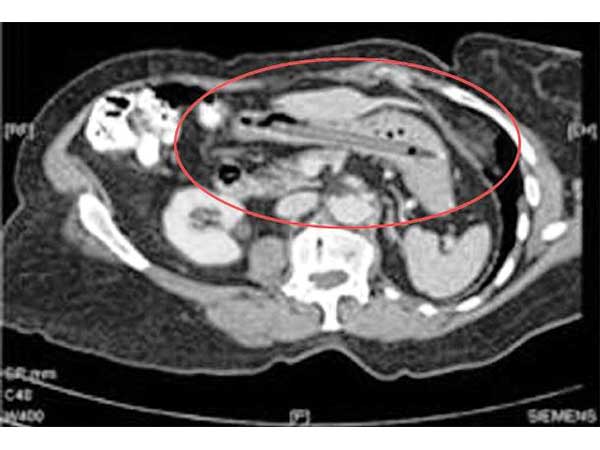

ಲೈಟ್ ಬಲ್ಬು

ಪಾಕಿಸ್ತಾನದ ಮುಲ್ತಾನ್ ನಗರದಲ್ಲಿ ಮದ್ಯ ತಯಾರಿಸಿದ ಆರೋಪದ ಮೇಲೆ ಫತೆಹ್ ಮೊಹಮ್ಮದ್ ಎಂಬಾತನನ್ನು ಜೈಲಿಗೆ ಹಾಕಲಾಗಿತ್ತು. ಪಾಕಿಸ್ತಾನದಲ್ಲಿ ಮದ್ಯ ತಯಾರಿಸುವುದೂ, ಸೇವಿಸುವುದೂ ಶಿಕ್ಷಾರ್ಹ ಅಪರಾಧವಾಗಿದೆ. ಈ ನಡುವೆ ಒಮ್ಮೆ ಬೆಳಿಗ್ಗೆ ಎದ್ದಾಗ ಆತನ ಆಸನದ್ವಾರದಲ್ಲಿ ಏನನ್ನೋ ಬಲವಂತವಾಗಿ ತುರುಕಿಸಿದ್ದುದು ಕಂಡುಬಂದಿತು. ಈತನನ್ನು ಪರೀಕ್ಷಿಸಿದ ಕಾರಾಗೃಹದ ವೈದ್ಯರು ಒಳಗೆ ಬಲ್ಬ್ ಒಂದದ ಭಾಗ ಇರುವುದನ್ನು ಕಂಡು ಅವಾಕ್ಕಾಗಿ ತಕ್ಷಣ ಮುಲ್ತಾನ್ ನ ನಿಶ್ತಾರ್ ಆಸ್ಪತ್ರೆಗೆ ಕಳುಹಿಸಿಕೊಟ್ಟರು. ಮುಂದಿನ ಸ್ಲೈಡ್ ಕ್ಲಿಕ್ ಮಾಡಿ

ಅಲ್ಲಿ ಉಪಸ್ಥಿತರಿದ್ದ ತಜ್ಞವೈದ್ಯ ಡಾ. ಫಾರುಖ್ ಆಫ್ತಾಬ್ ತಕ್ಷಣವೇ ಶಸ್ತ್ರಕ್ರಿಯೆಯ ಮೂಲಕ ಬಲ್ಬ್ ಒಡೆಯದಂತೆಯೇ ಹೊರತೆಗೆಯಲು ಯಶಸ್ವಿಯಾದರು. ಏಕೆಂದರೆ ಮಾಂಸಖಂಡಗಳ ಒತ್ತಡದಿಂದ ಒಂದು ವೇಳೆ ಬಲ್ಬ್ ಒಡೆದರೆ ಅದರ ಚೂರುಗಳೆಲ್ಲಾ ಕರುಳನ್ನು ಛಿದ್ರವಾಗಿಸುವ ಸಂಭವವಿತ್ತು. ಅಚ್ಚರಿ ಎಂದರೆ ಇದು ಈತನೊಳಗೆ ಬಂದಿದ್ದಾದರೂ ಹೇಗೆ ಎಂಬುದಕ್ಕೆ ಈತನಲ್ಲಿ ಯಾವುದೇ ಉತ್ತರವಿಲ್ಲ. ಬಹುಷಃ ಯಾರೋ ಸೇಡು ತೀರಿಸಿಕೊಳ್ಳಲು ಈ ಕ್ರಮ ಕೈಗೊಂಡಿರಬಹುದು ಎಂದು ಪೋಲೀಸರು ಅನುಮಾನಿಸಿದ್ದಾರೆ.